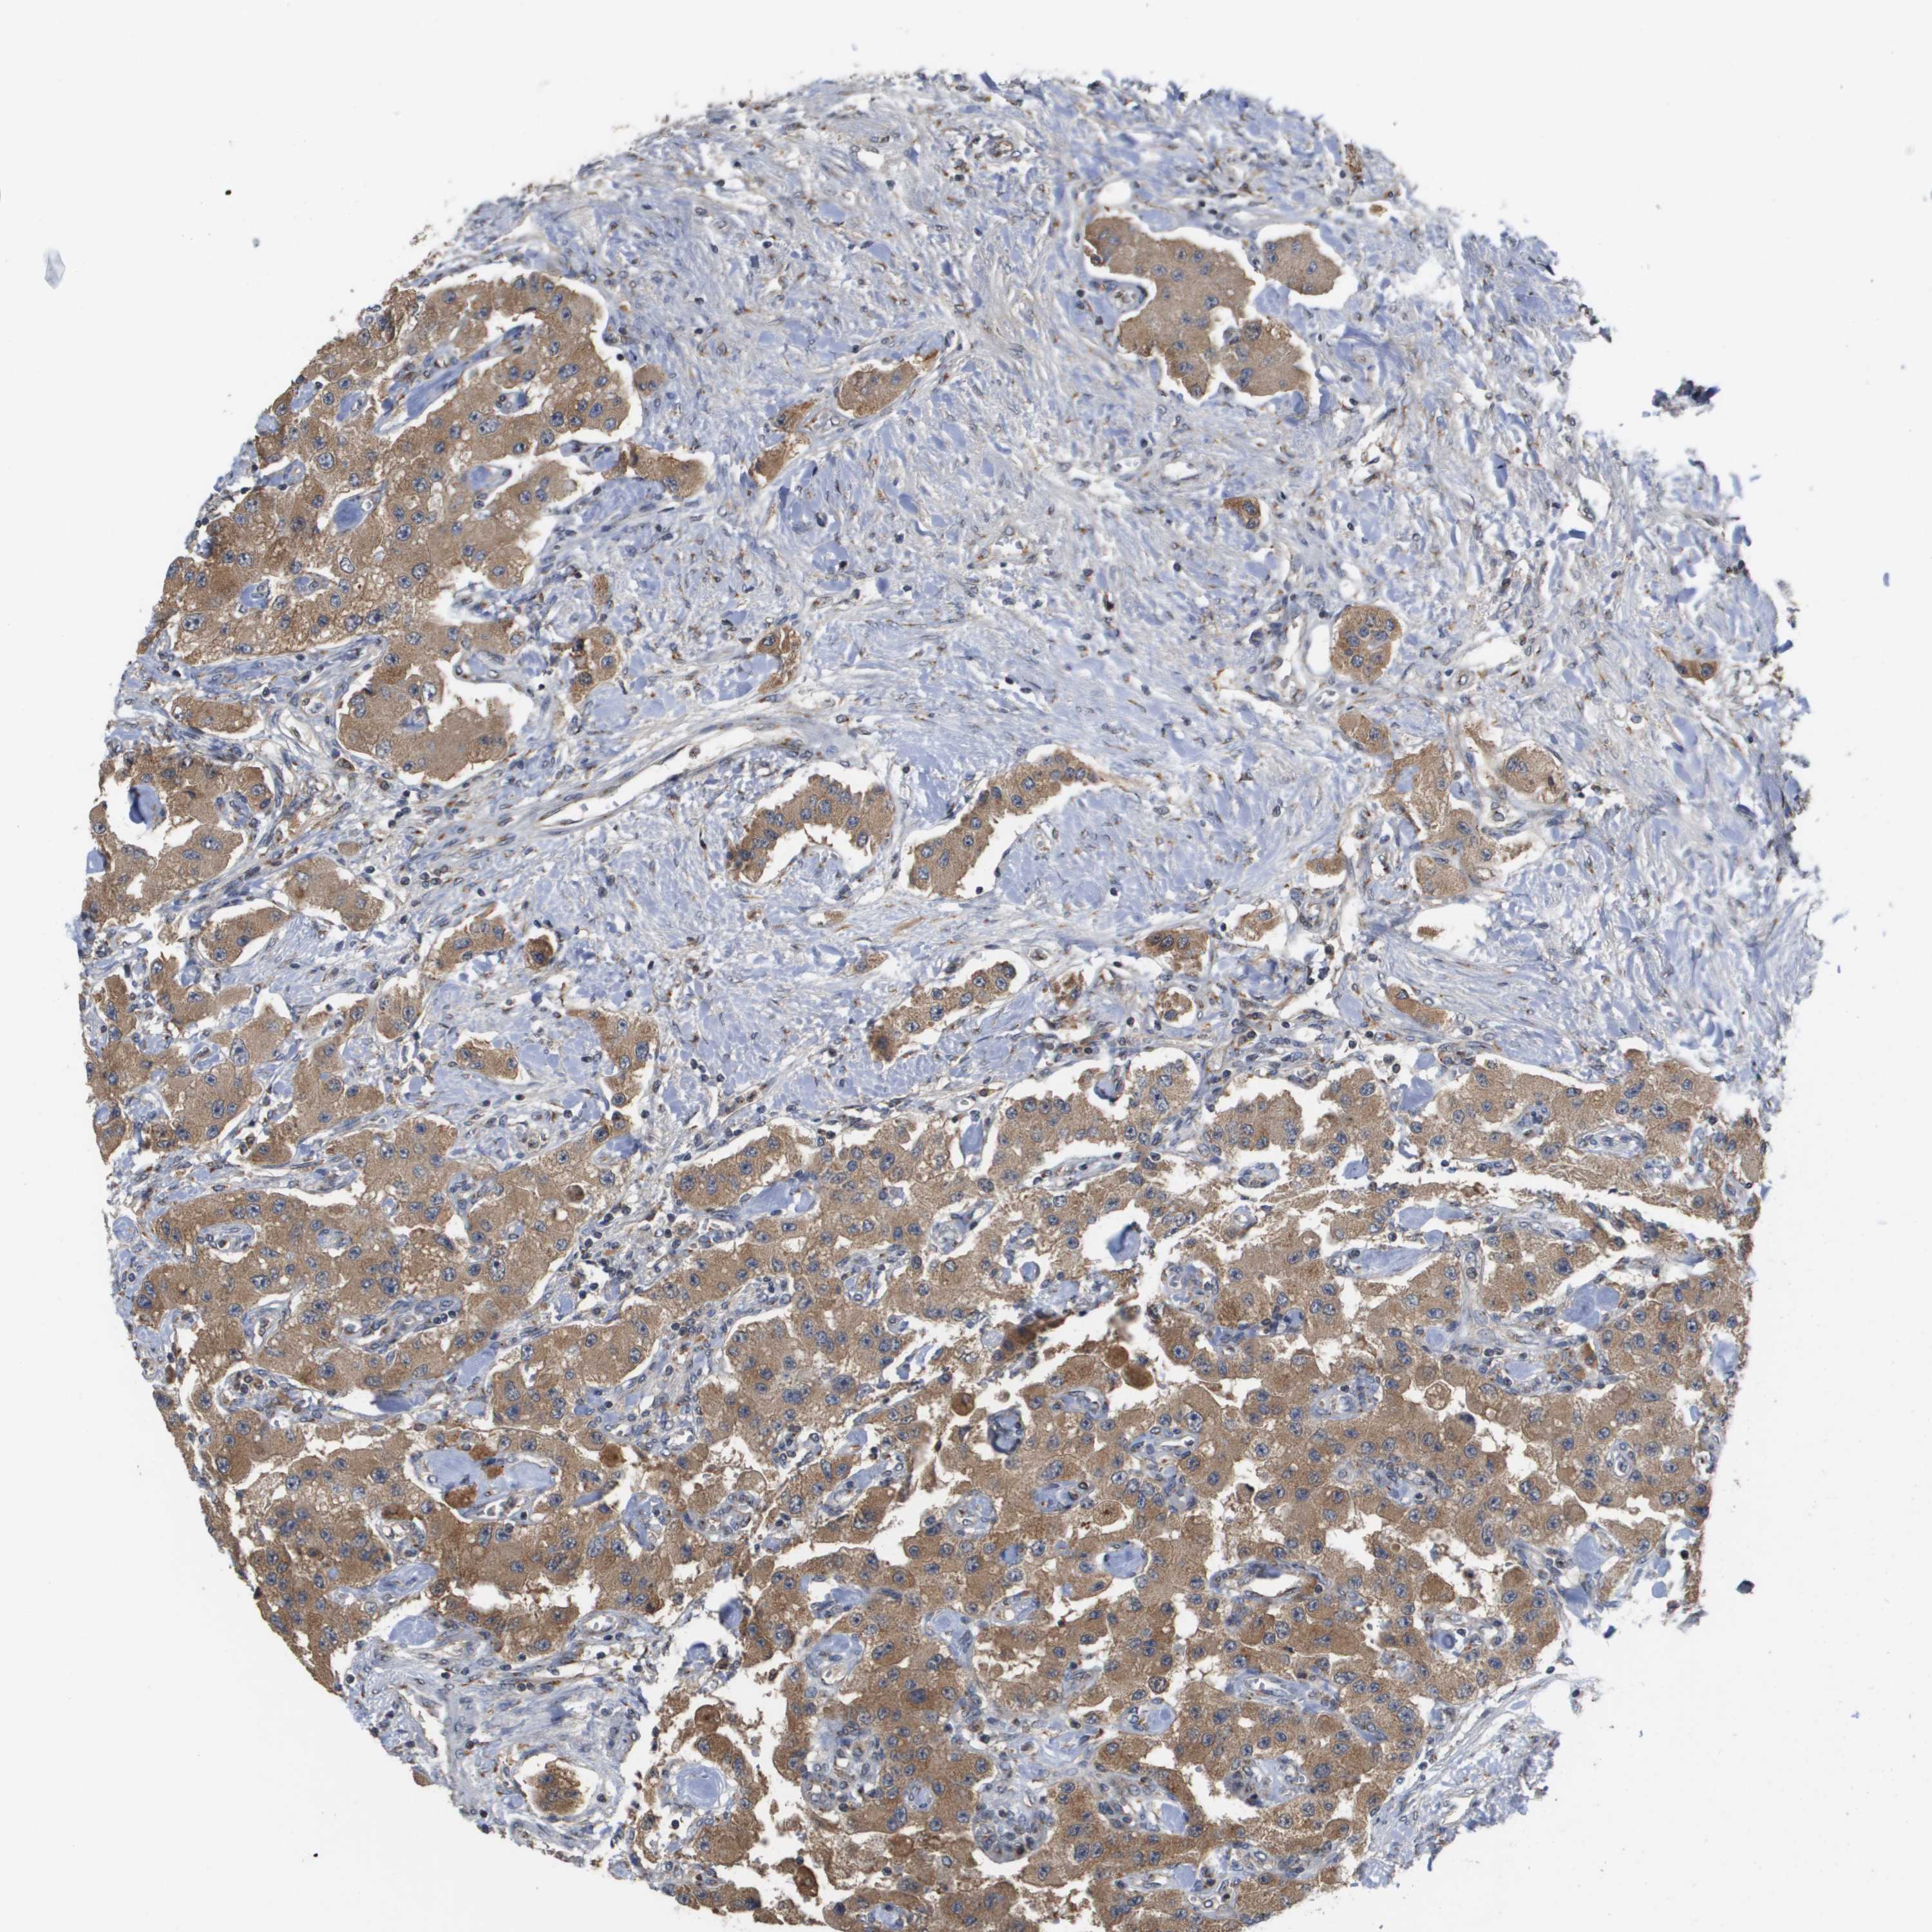

CARCINOID - Protein expressioni

A mouse-over function shows sample information and annotation data. Click on an image to view it in a full screen mode. Samples can be filtered based on level of antibody staining by selecting one or several of the following categories: high, medium, low and not detected. The assay and annotation is described here.

Antibody stainingi

Antibody staining in the annotated cell types in the current human tissue is reported as not detected, low, medium, or high, based on conventional immunohistochemistry profiling in selected tissues. This score is based on the combination of the staining intensity and fraction of stained cells.

Each image is clickable and will lead to virtual microscopy that enables deeper exploration of all samples and also displays staining intensity scores, fraction scores and subcellular localization as well as patient and tissue information for each sample.

Antibody HPA006277

Antibody HPA006507

Antibody CAB017027

Staining

High

Medium

Low

Not detected

Intensity

Strong

Moderate

Weak

Negative

Quantity

>75%

75%-25%

<25%

None

Location

Nuclear

Cytoplasmic/membranous

Cytoplasmic/membranous,nuclear

Carcinoid, malignant, NOS